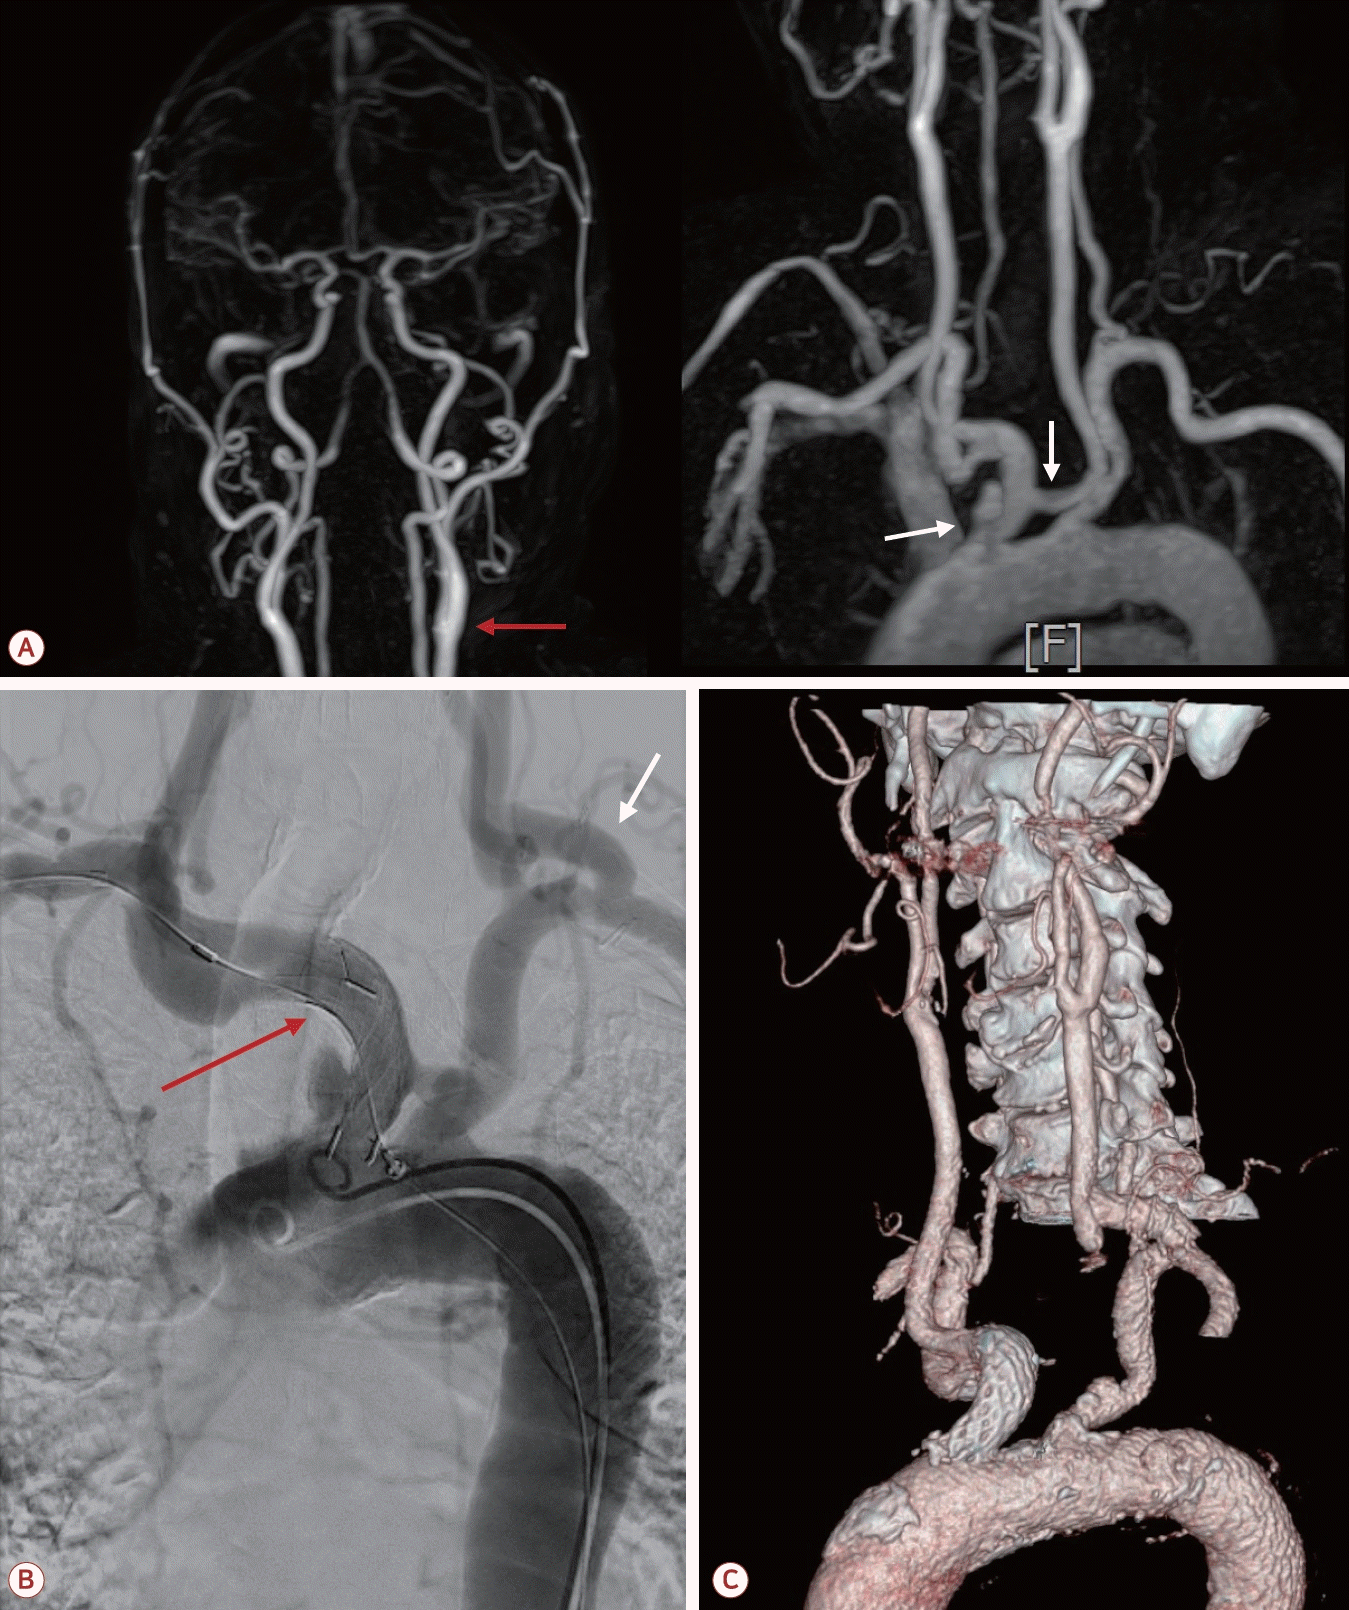

73세 남자가 최근 3개월간 반복적인 허혈뇌졸중으로 내원하였다. 환자는 고혈압, 당뇨, 안정협심증의 기저 질환을 가지고 있었다. 초기 뇌자기공명영상(magnetic resonance [MR] imaging)에서 좌측 대뇌반구와 우측 소뇌에 다발성 허혈 병변이 관찰되었으며(Fig. 1-A) 혈관 검사에서는 좌측 내경동맥근위부(internal carotid artery, ICA)에 76.7%의 협착(NASCET 기준)이 확인되었고 동시에 보바인형 대동맥궁(bovine arch, 공통 기시형 변이)이 관찰되었다(Fig. 1-B). 이에 따라 증상성 중증도 이상의 ICA 협착으로 판단하여 좌측 CEA와 이중 항혈소판 요법이 시행되었다. 그러나 시술 2개월 후에 우측 후 대뇌동맥(posterior cerebral artery, PCA)과 우측 중대뇌동맥(middle cerebral artery, MCA) 영역에 재발성 뇌경색이 발생하였고(Fig. 2-A) 한 달 후에는 좌측 MCA와 PCA 영역에 새로운 뇌경색이 재발하였다(Fig. 2-B). 기존에 진행되었던 두개경유도플러 검사에서 심방중격 결손이나 미세색전 신호를 시사하는 소견은 확인되지 않았고 흉부경유심초음파에서 좌심실 박출률은 정상 범위었으며 3일의 홀터 모니터링에서도 심방세동은 관찰되지 않아 심장성 색전은 배제하였다. 반복되는 색전성 병변의 원인을 찾기 위하여 식도유심초음파(transesophageal echocardiography, TEE)가 진행되었으며 대동맥궁 대만부(greater curvature)에 위치한 7 mm 크기의 궤양성(ulcerated), 유동성(mobile)의 고위험 죽경화판(high-risk aortic arch plaque)이 관찰되었다(Fig. 2-C). 추가적인 머리 혈관조영에서는 기존에 확인되었던 좌측 경동맥의 중증도 협착은 호전 상태를 보였으며 보바인형 대동맥궁 및 팔머리동맥에 동맥류성 확장(aneurysmal dilatation)을 확인할 수 있었다(Fig. 3-A). 이에 신경과, 순환기내과, 영상의학과, 심장혈관흉부외과가 포함된 다학제 협의를 통해 단계적 하이브리드 치료가 결정되었다. 첫 번째 단계로 부분 디브랜칭 수술(좌쇄골하-좌총경동맥우회술[partial debranching surgery, left subclavian-left common carotid artery bypass])이 시행되었다. 수술 한 달 후에 팔머리동맥에 스텐트이식편(endovascular brachiocephalic stent-graft)을 삽입하여 팔머리동맥류의 병적 분절을 제거하였다(Fig. 3-B, C). 스텐트 시술 이후 약 1년 6개월이 지난 현재까지도 환자는 지속적으로 이중항혈소판 요법을 유지하면서 추가적인 허혈 사건 없이 안정적으로 추적 관찰 중이다.

(A) Initial brain MR imaging showing multiple small acute ischemic lesions in the left cerebral hemisphere and right cerebellum. (B) Initial MR angiography demonstrating 76.7% stenosis (as calculated in NASCET) of the left proximal internal carotid artery (red arrows) and bovine aortic arch (white arrow). MR; magnetic resonance, NASCET; North American symptomatic carotid endarterectomy trial, MRI; MR imaging.